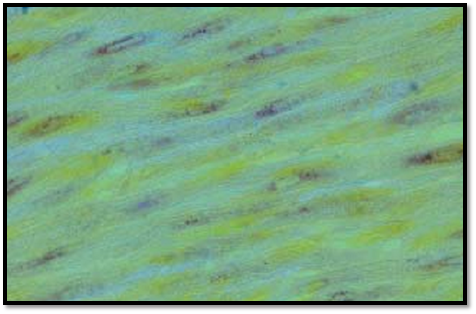

The cardiomyocytes of the atrium contain osmiophilic granules. These specific granulate d atrial cells execute endocrine functions and are therefore called myoendocrine cells . They secrete the heart polypeptide hormone atrial natriuretic polypeptide (ANP) (also known as cardiodilatin (CDD), cardionatrin and atriopeptin). The hormone plays an important role in the regulation of the blood pressure and the water-electrolyte balance (diuresis natriuresis). This figure shows myoendocrine cells from the atrium dextrum of a pig heart after peroxidase-antiperoxidase staining using an antibody against cardiodilatin. The brown products of these reactions are pre dominantly found in the sarcoplasmic cones of the cells (perinuclear localization ). Farther away from the nucleus, staining is weaker. Myoendocrine cells occur in small numbers also in the ventricular myocardium. There, they are detected along the excitatory tissue in the septum.

Preparation; magnification: × 380